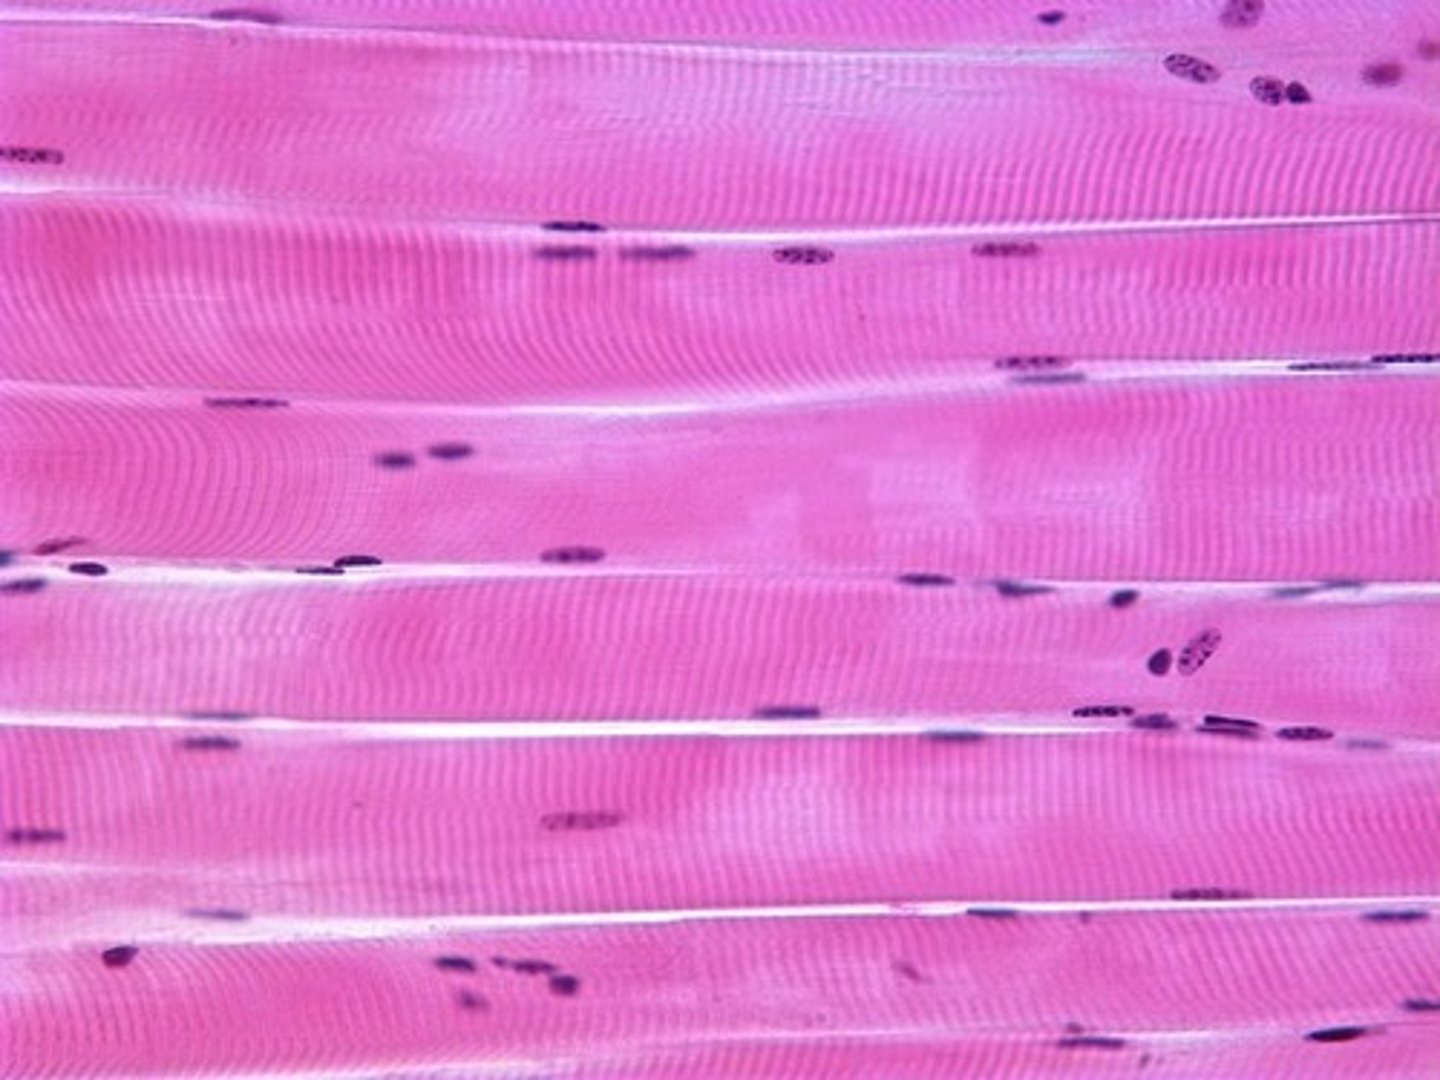

skeletal muscle is

a. striated

a. striated

skeletal muscle

skeletal muscle is ______-nucleated

multi-nucleated

skeletal muscle is under ____ control

voluntary